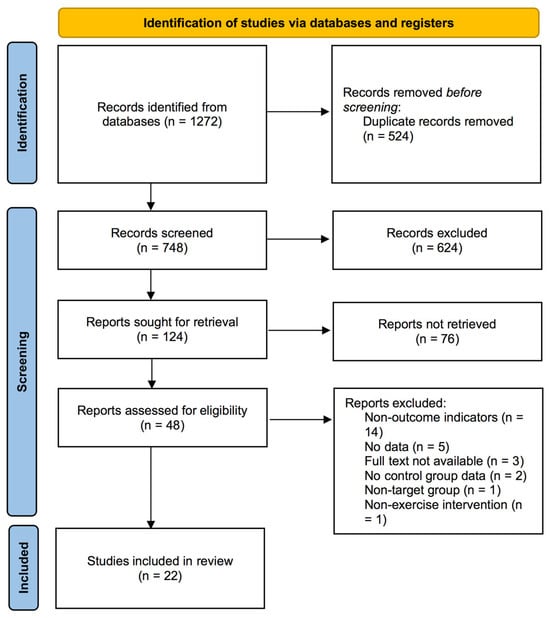

Objectives: This study sought to evaluate the impact of exercise on balance function in individuals with knee osteoarthritis (KOA) and determine the most effective exercise protocols for balance enhancement. Methods: A systematic literature search was performed across five major electronic databases

Objectives: This study sought to evaluate the impact of exercise on balance function in individuals with knee osteoarthritis (KOA) and determine the most effective exercise protocols for balance enhancement. Methods: A systematic literature search was performed across five major electronic databases (PubMed, Web of Science, EBSCO, Cochrane, Scopus) until 13 September 2024. Statistical synthesis was conducted using weighted mean differences (WMDs) with 95% confidence intervals under a random-effects model. Results: Analysis of 22 studies revealed significant improvements in balance function following exercise interventions. Outcomes measured by the Berg balance scale (BBS, WMD, 2.65, p < 0.00001) and timed up and go test (TUG, WMD, −0.59, p < 0.0001) demonstrated clinically relevant enhancements in KOA populations. Subgroup analyses revealed that multicomponent training (WMD, 6.25, p = 0.003), interventions lasting ≥ 8 weeks (WMD, 4.92, p = 0.002), sessions ≥ 60 min (WMD, 7.42, p = 0.002), frequency ≥ 3 times per week (WMD, 2.83, p = 0.0005), weekly time ≥ 180 min per week (WMD, 7.42, p = 0.002), and patients < 60 years (WMD, 6.71, p = 0.002) were associated with greater improvement in BBS. Conclusions: Exercise significantly improved balance function in KOA patients, with multicomponent training emerging as the most effective intervention. Based on the findings of this meta-analysis, clinicians should recommend that KOA patients engage in exercise at least three times per week, with each session lasting at least 60 min, to achieve a total weekly time of 180 min. These recommendations are particularly relevant for patients less than 60 years, who may experience greater benefits from exercise interventions.

Figure 1